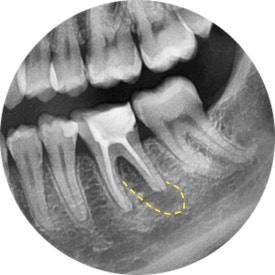

파노라마 엑스레이로 전체 치아들을 조망하겠습니다.

역시나...

왼쪽 아래에 신경치료 받은 치아가 심상치 않아보이네요.

파노라마를 확대해보니,

앞선 프랑스 유학생의 사례와 마찬가지로

이전에 신경치료 받은 치아에서 염증이 시작되고 있었습니다.

왜일까요?

곧이어 치근단엑스레이를 찍어보았지요.

어금니는 뿌리가 여러개기 때문에, 경우에 따라 각도를 달리하여

2장 이상 촬영하기도 한답니다.

통상 아래 어금니에는 신경이 4개 (적으면 3개, 많으면 5개) 있게 마련이죠.

그런데 조금 이상합니다.

4개 중에 2개가 뿌리 전체 길이에 못미치게 치료가 되어 있습니다.